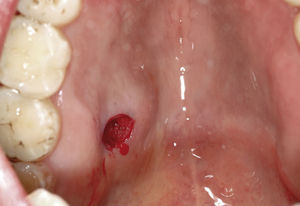

Dos terceras partes de los tumores de las glándulas salivales menores afectan a mujeres y una tercera parte a hombres. Estos tumores pueden aparecer en cualquier etapa de la vida, pero la edad media en el momento de la aparición se sitúa entre los 40 y los 60 años. La localización más frecuente es el paladar duro en su tercio posterior, seguido del paladar blando y de la mucosa del labio inferior. Sin embargo, pueden aparecer también en la mucosa yugal y en el trígono retromolar13. Por regla general, la sintomatología clínica no es llamativa y, con frecuencia, sólo se observa una ligera tumefacción que es indolora a la palpación. Además, los tumores de las glándulas salivales menores se caracterizan por un creci-miento lento y se manifiestan en forma de nódulos tisu-lares duros, desplazables, situados debajo de la mucosa intacta. Se pueden observar también pequeñas tramas vasculares sobre el tumor o en los márgenes del mismo.

La aparición de úlceras, alteraciones sensitivas y trastor-nos del habla es excepcional.

La tasa alta de recidivas (5–30%) es característica de este tipo de tumores debido sobre todo a una escisión quirúrgica incompleta. Reichart et al14 presentaron recientemente un caso de un carcinoma incluido en un adenoma pleomórfico de una glándula salival menor. Estos casos son extraordina-riamente raros y sólo se pueden detectar mediante exáme-nes histopatológicos minuciosos. Después del tratamiento quirúrgico de un tumor de glándulas salivales están indica-dos controles postoperatorios periódicos.